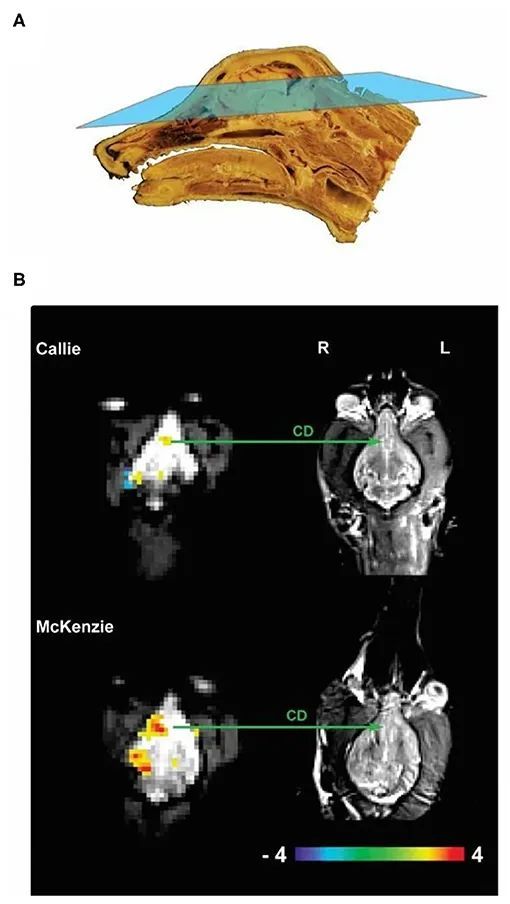

研究结果显示,狗狗在听到表扬语调的表扬词时,大脑奖赏系统——中脑边缘多巴胺系统的激活显著地高于其他3种情况。

狗狗看到奖赏手势后大脑的变化